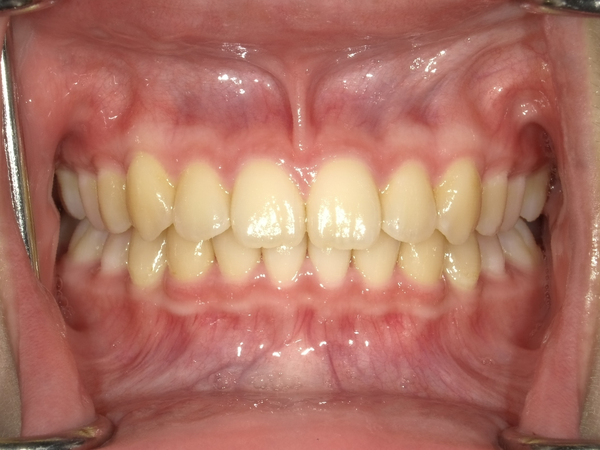

すきっぱ(空隙歯列)CASE5 2023.06.19 10代女性非抜歯〇ご相談内容:上前歯のすきっぱ〇矯正の種類:マウスピース型矯正「インビザラインGO」〇治療期間:14週間〇治療費用:44万円(税込) < すきっぱ(空隙歯列)CASE6すきっぱ(空隙歯列)CASE4 > ブログ記事一覧をみる